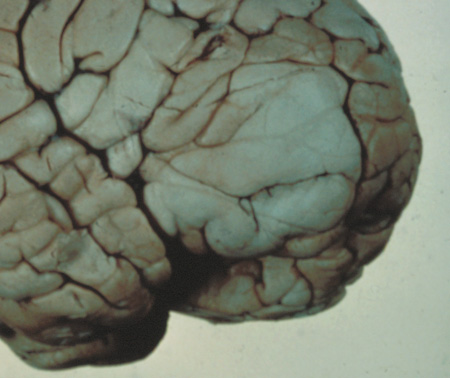

1. Superficial cortical sclerosis (parenchymal hamartoma) which distort the gyri. Microscopy shows large atypical fibrillary type astrocytes with few associated neurons and areas of calcification.133 The numerous abnormal glial processes and fibers make the tissue abnormally firm or “sclerotic” on palpation (Fig. 13).132

Fig. 13. Tuberous Sclerosis Complex: “cortical sclerosis.” Numerous abnormal glial processes make the tissue abnormally firm or “sclerotic” on palpation.132